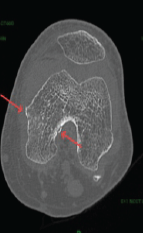

Medial Hoffa’s Fracture Treated with Subvastus Approach – Case Series

Parimal Vairagade , Akhilesh Khobragade , Devashis Barick , Kunal Parmar , Darshan Sharma , Shrikrishna Rakhunde ………………………………p.141-145